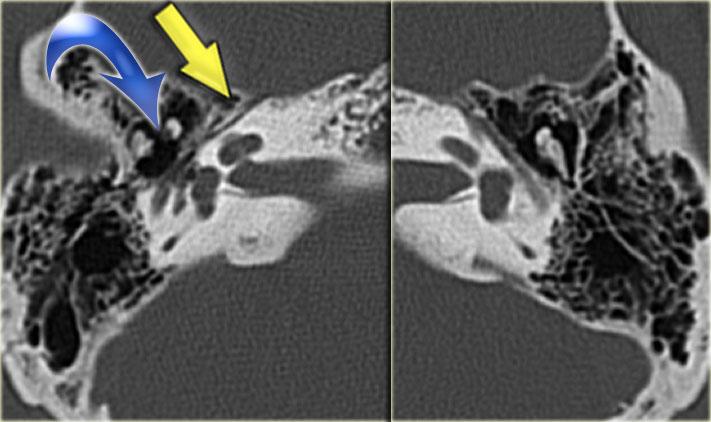

Bên trái là hình ảnh của một bé trai 16 tuổi, được khám tiền phẫu vì cholesteatoma tai phải.

Là một phát hiện tình cờ, có hình ảnh ống bán khuyên ngoài phình to (mũi tên vàng) và vắng mặt ống bán khuyên trên (mũi tên xanh dương).

Tại vị trí dự kiến của ống bán khuyên trên chỉ quan sát thấy một gờ nhỏ.

Ống bán khuyên sau bình thường.